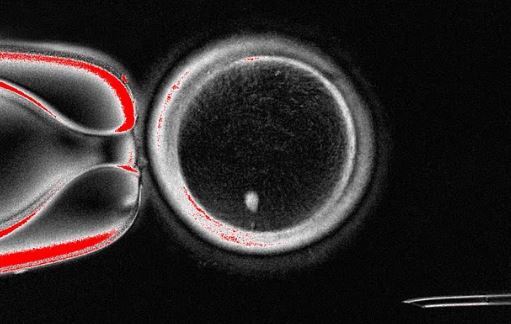

در جریان آزمایشها، محققان توانستند با استفاده از این فرآیند ۸۲ تخمک سالم را تولید کنند که سپس در آزمایشگاه بارور شدند. تقریباً ۹ درصد از این تخمکها به مرحله بلاستوسیست (مرحله خاصی از رشد جنین) رسیدند. با این حال، محققان بلاستوسیستها را پس از این مرحله کشت ندادند که این زمان مصادف با زمانی است که معمولاً در درمان IVF به رحم منتقل میشوند.

با وجود اینکه این یافتهها امید تازهای به زنانی میدهد که مشکلات تخمک دارند تا بتوانند فرزندانی با ژنتیک خودشان داشته باشند، اما کارشناسان به چندین نقص در این مطالعه اشاره کردهاند. نکته مهم این است که بخش عمدهای از آنها (۹۱ درصد) پس از لقاح، رشد نکرده و متوقف شدند. علاوه بر این، در تعدادی از بلاستوسیستها اختلالات کروموزومی مشاهده شد.